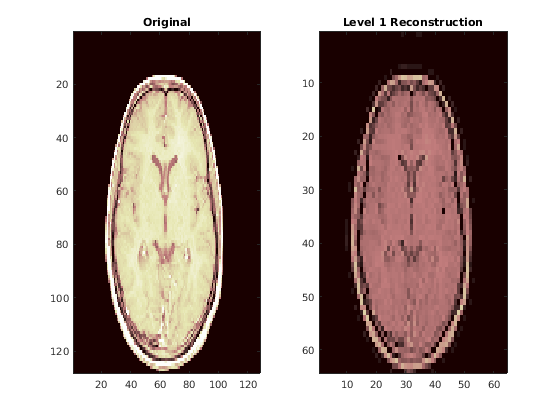

Сравните реконструкцию среза с исходной версией.

figure colormap(map) subplot(1,2,1) image(X(:,:,num)) title("Original") subplot(1,2,2) image(xrs) title("Level 1 Reconstruction")